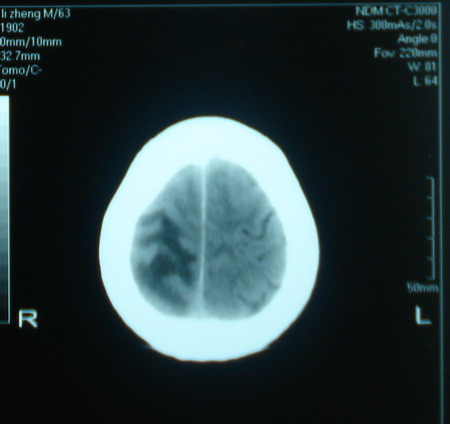

标题: CT13794:M63Y,头颅CT平扫 [打印本页]

标题: CT13794:M63Y,头颅CT平扫

男,63岁,头痛,呕吐,意识模糊一周。无发烧及感染史。

脑膜瘤可能。建议增强或mr检查

支持恶性胶质瘤,增强

胶质母细胞瘤可能,建议增强扫描。

胶质瘤可能性大,建议增强扫描。

支持右侧丘脑恶性胶质母细胞瘤可能性大,建议增强进一步检查。